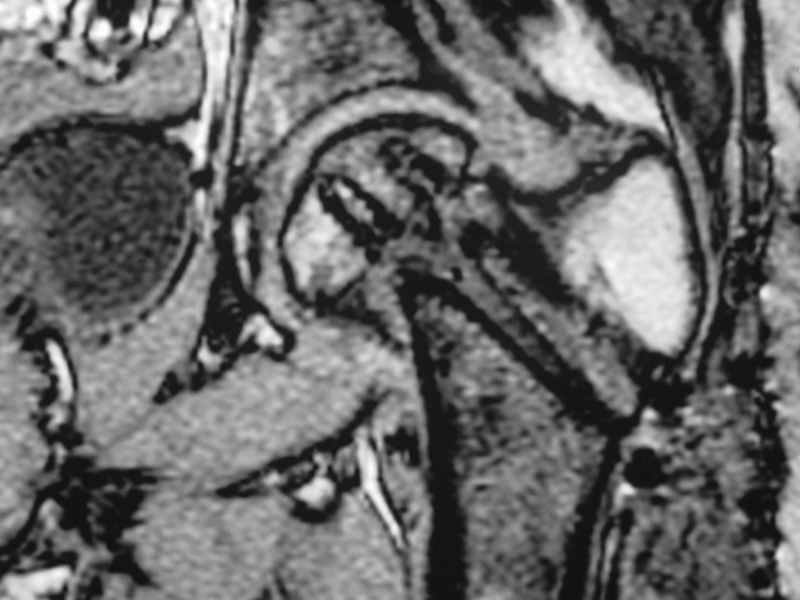

Erden K?l?c 16 Октябрь 2005, 00:03

I would leave it as it is. Because surgical intervention will not be able to prevent osteonecrosis if it is going to be. MRI may be helpful to determine union if there is any and also gives an idea about the viability of the head.

Stephen Kottmeier 17 Октябрь 2005, 21:05

friend

dhs will not correct improper biomechanical environment and may further compromise vascular

integrity consider establish vascular status via mri

and if viable follow with proximal valgus osteotomy

Отправитель: Peter Trafton 17 Октябрь 2005, 21:21

I think that this 31 yo deserves a try with valgus osteotomy, as so nicely illustrated by stephen kottmeier. However, I'd do it no matter what an MRI shows - thus why bother with the MRI? (What sort of data support MRI's ability to predict segmental collapse?)